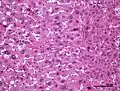

Hepatic adenomas are, typically, well-circumscribed nodules that consist of sheets of hepatocytes with a bubbly vacuolated cytoplasm. The hepatocytes are on a regular reticulin scaffold and less or equal to three cell thick.

The histologic diagnosis of hepatic adenomas can be aided by reticulin staining. In hepatic adenomas, the reticulin scaffold is preserved and hepatocytes do not form layers of four or more hepatocytes, as is seen in hepatocellular carcinoma.

Cells resemble normal hepatocytes and are traversed by blood vessels but lack portal tracts or central veins.

Micrograph of hepatic adenoma. H&E stain

Micrograph of hepatic adenoma. H&E stain -

Micrograph of hepatic adenoma. Reticulin stain

Micrograph of hepatic adenoma. Reticulin stain -